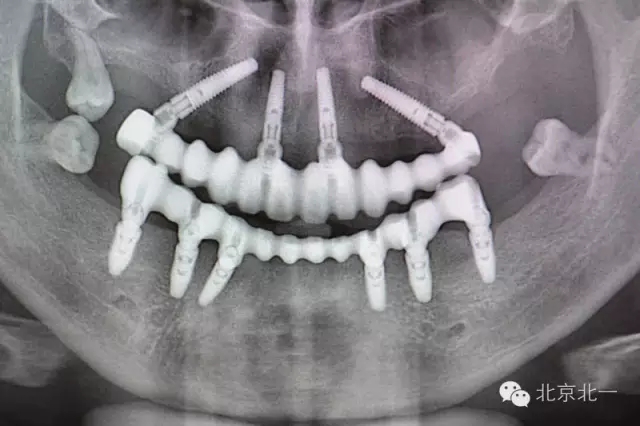

圖三、四:術(shù)中植入四枚植體,長度15mm。角度復(fù)合基臺

圖五:術(shù)后全景片

圖八:戴牙后復(fù)查全景片